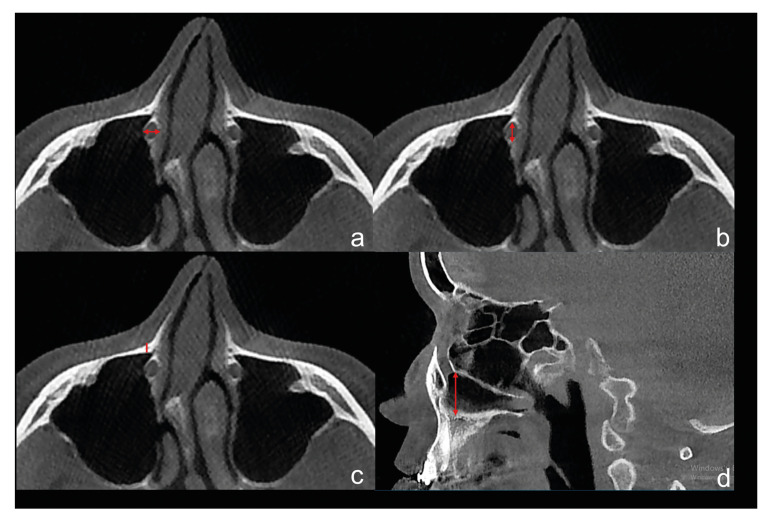

Material and methods: The authors conducted a retrospective cohort study consisting of patients who underwent Le Fort I osteotomies between 2017 and 2021 in the Erciyes University Faculty of Dentistry. The primary predictor variables were the distance of the nasolacrimal canal to the outer cortex of the maxilla and the nasal floor, as well as the superior-inferior level of the superiorly positioned screw inserted in the maxilla aperture region relative to the nasolacrimal canal. The outcome variable was the presence of a nasolacrimal duct injury. Mann Whitney U test was used for quantitative variables between the two groups. A Pearson chi-squared analysis was used to compare categorical data. A p-value <0.05 was considered statistically significant.

Results: A total of 290 nasolacrimal canals were evaluated in 145 patients, 87 females, and 58 males. The mean age was 23.47± 6.67. There was a statistically significant relationship between screw level and nasolacrimal canal perforation (p<0,001). The distance between the most anterior border of the nasolacrimal canal and the outer cortical of the maxilla was significantly less in the perforation group (p<0,001). The fixation screw was significantly closer to the nasolacrimal canal in the perforation group (p<0,001).

Conclusions: In Le Fort I surgery, nasolacrimal duct injury may occur during screw fixation to the aperture region. Superiorly positioned fixation screws in the aperture region may damage the nasolacrimal canal. In patients where the nasolacrimal canal is close to the outer cortex, care should be taken when applying the fixation screws to the aperture region to avoid damaging the canal.